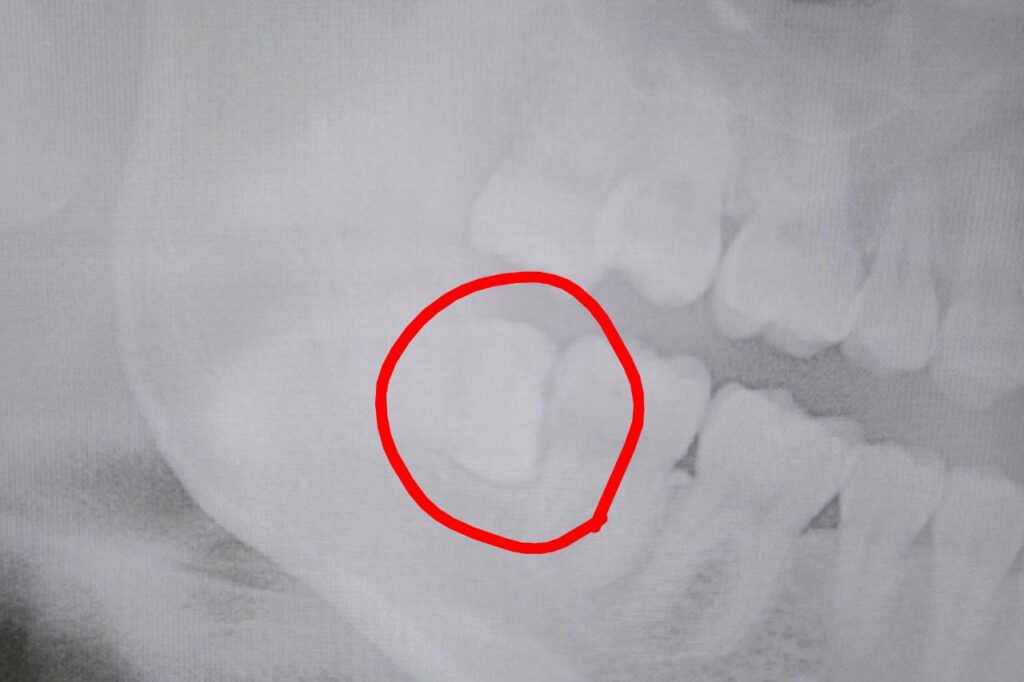

こちらは私の去年のレントゲン画像。上下左右とも1番奥に親知らずがあり、特に下の親知らずは左右とも真横を向いて少しだけ生えてる状態でした。ドクターや衛生士からは度々「抜いた方が良いよ!」と言われてました。それはなぜか……?🤔

このような親知らずは奥までブラシが当たりにくく汚れが残りやすかったり、手前の歯とぶつかっていることによって歯間の虫歯になりやすい状態でした💦